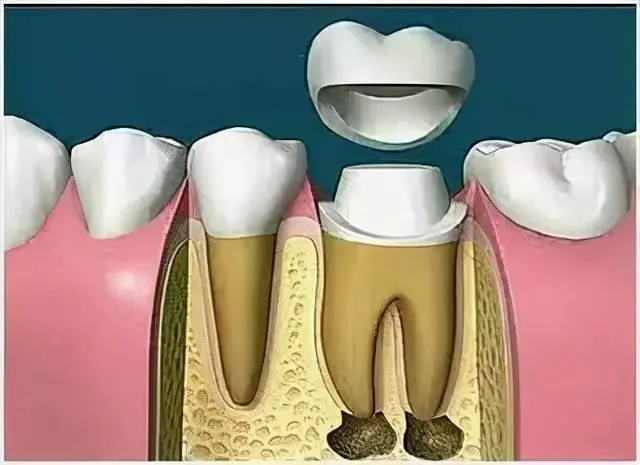

根管治疗后为什么还需要做全冠保护?

很多病人不理解,为什么在根管治疗后,牙齿不疼了,补上就可以了,为什么还要做全冠保护,觉得没有必要。

事实上在根管治疗后,没有牙髓提供营养的牙齿会变暗、变脆,剩余的牙冠部分很容易折断劈裂,导致牙齿使用寿命减少,因此根管治疗后需做全冠对其进行保护。